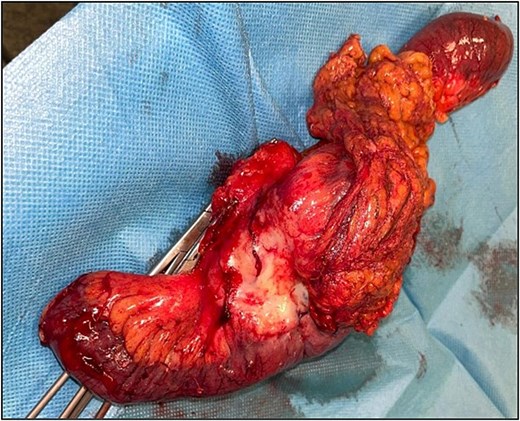

The patient underwent an exploratory laparotomy with segmental enterectomy of approximately 30 cm of jejunum (Fig. 7) and Hartmann’s procedure with partial mesorectal excision. The postoperative course was complicated with a pelvic abscess, managed with CT guided percutaneous drainage and antibiotic therapy. The patient was discharged on the 23rd postoperative day.

The histopathological examination revealed:

(1) jejunal mucinous adenocarcinoma with serosal involvement, lymphovascular and perineural invasion, without metastasis in the 16 lymph nodes examined; and

(2) mesorectal tumoral deposit, without ulceration of the rectal mucosa, with lymphovascular and perineural invasion and no metastasis in the 19 lymph nodes examined, consistent with metastasis from SB adenocarcinoma.

Clear margins were observed in both specimens. Staging: pT4 N0 LVI+ PNI+ R0 M1.